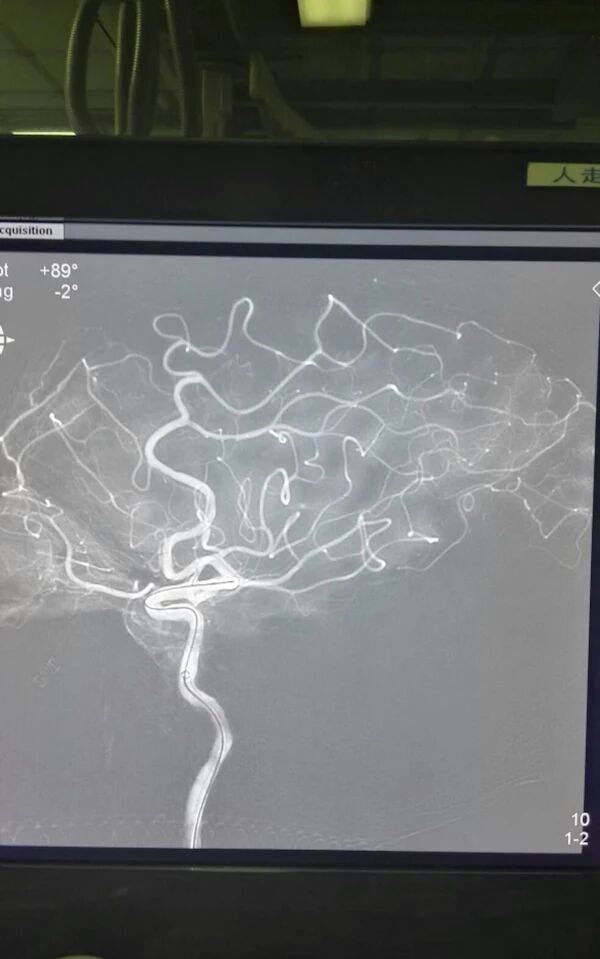

完善相关检查后,急诊行全脑血管造影术

示右侧大脑后动脉P1段不显影,右侧后交通动脉开放。左侧P1中段闭塞,左侧前循环无明显代偿。考虑该血管为责任血管,急诊行血管开通术。